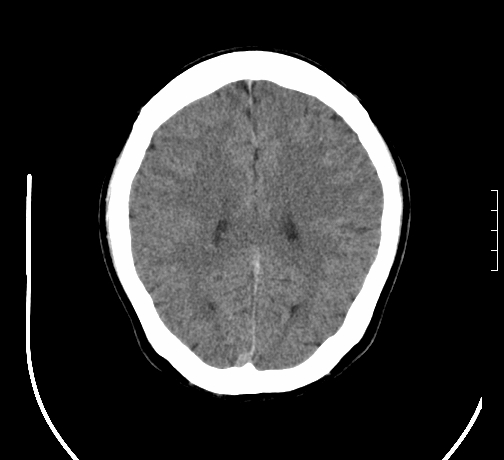

小脑发育畸形?

小脑萎缩。

考虑小脑发育不良,建议mri检查。

考虑小脑发育不良伴小脑萎缩,建议mri检查。

小脑萎缩,原因待查,建议mri检查。

考虑药物性小脑萎缩